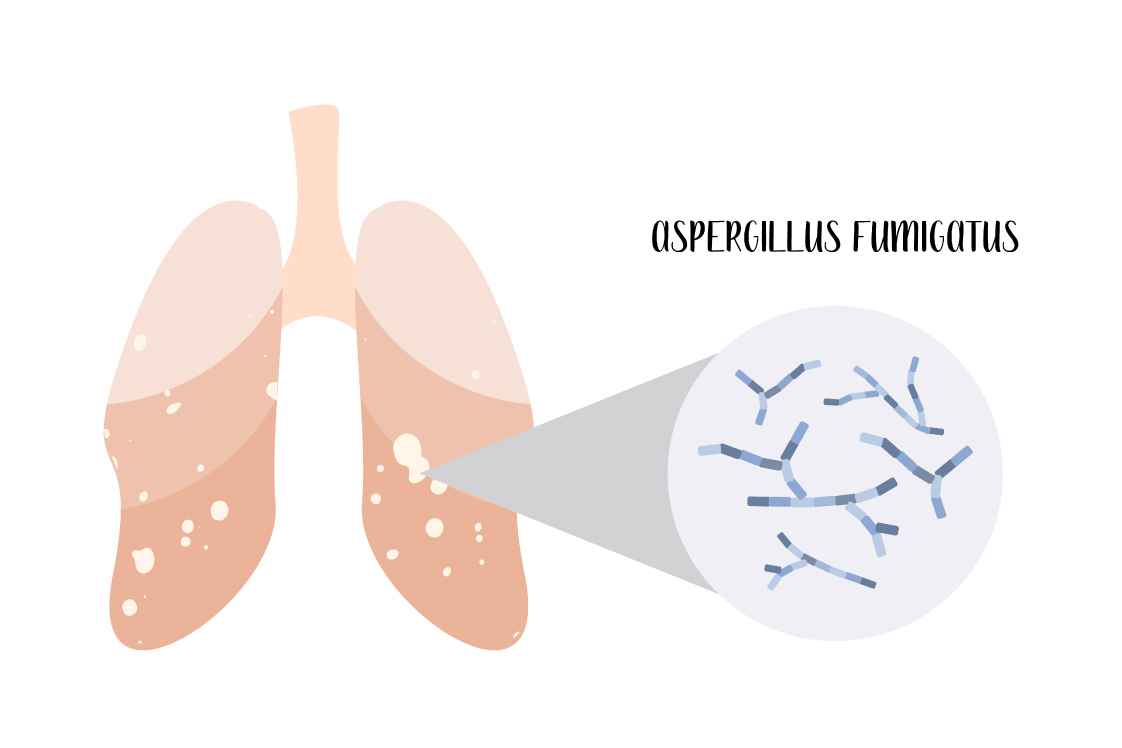

肺アスペルギルス症

アスペルギルス(真菌の種類)による肺真菌症は、侵襲性、慢性、単純性、アレルギー性の4つのタイプに大別されます。これらは、それぞれ異なる基礎疾患、経過、治療法を持っており、正確な診断と適切な治療が重要です。